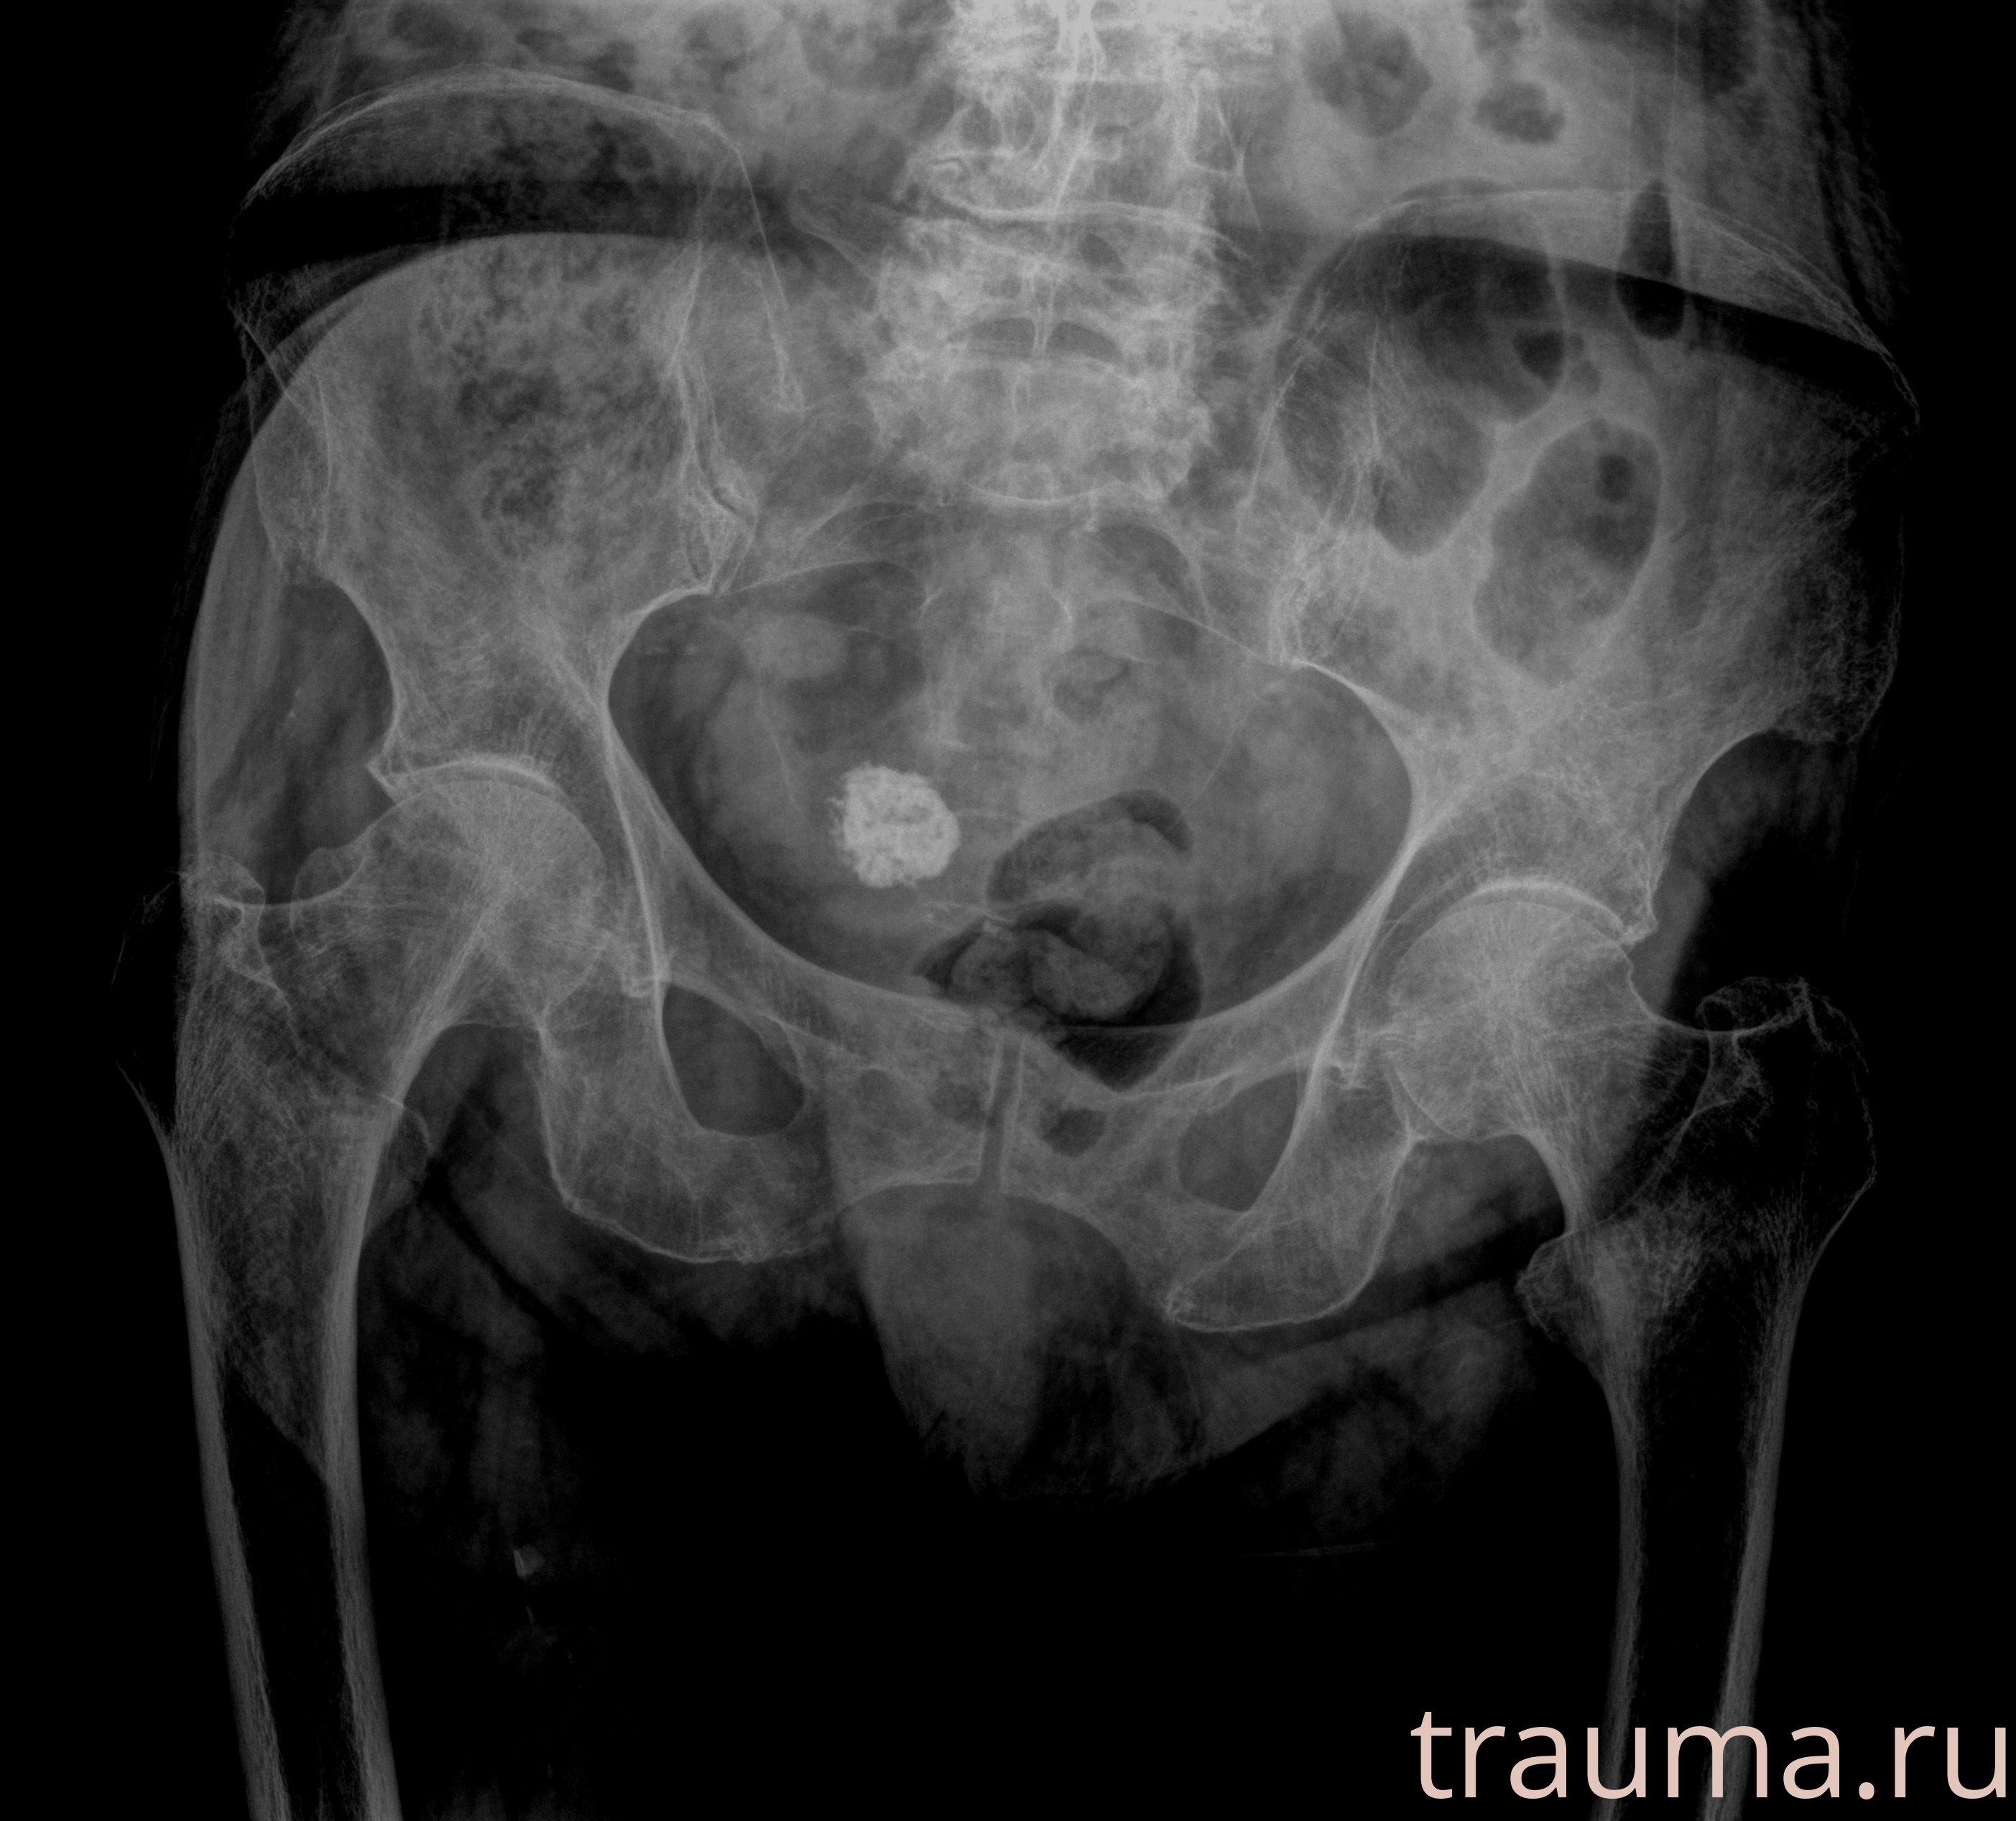

Рентген на дому: по вашему адресу приезжает врач-рентгенолог, травматолог-ортопед с мобильным рентгеновским аппаратом, проводит диагностику травмы или заболевания, делает необходимые рентгенограммы, дает рекомендации по дальнейшему лечению. Получить качественные снимки в домашних условиях возможно благодаря уникальной методике, разработанной МосРентген Центром для института  Склифосовского